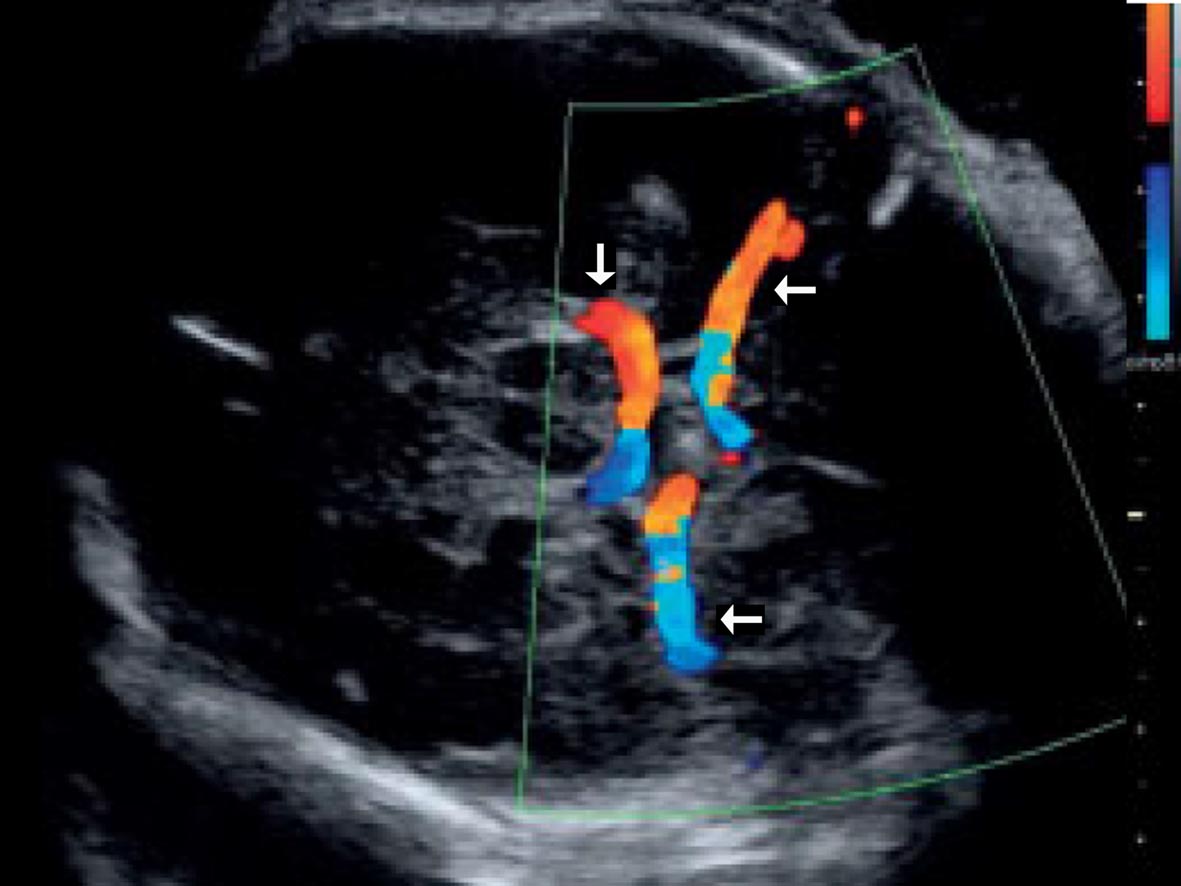

(2)颅底横切面:在获得丘脑水平横切面后,声束平面略向颅底方向平行移动即可显示颅底横切面(图7-3),在此切面上可见到大脑脚、第三脑室、TV下角、WILLS环及其大脑前、中(←)、后(↓)动脉等结构。

图7-3胎头颅底横断面声像图